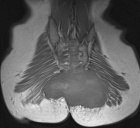

25 y/o male with chronic coccygeal pain who presents with progressive left buttock mass. Mild constipation. No other complaints. Smoker, otherwise healthy.

PE: Large, nontender mass involving L>R buttock with induration and erythema. Neurovascularly intact

Zoom image: Radiological image Radiological image.